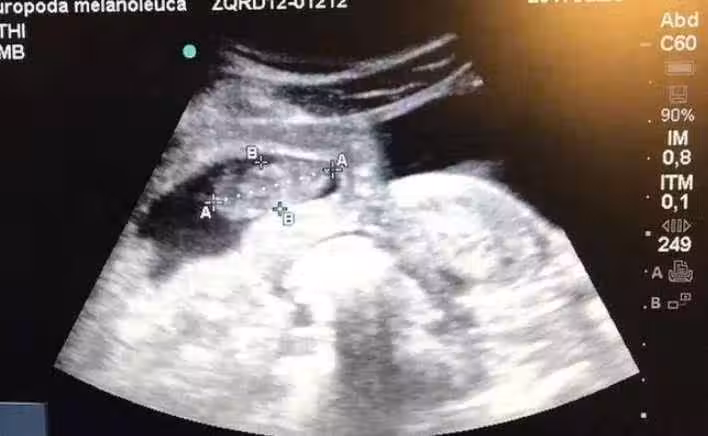

就算畸形也認了,懷孕查出是連體嬰,家人反對不讓生,孕媽偷偷生下後:全家都淚流不止

讓我趕緊跟家人商量,我當時很害怕,不知道怎麼辦。

婆家人知道後都讓我把孩子打掉,就連老公都反對我生下來,

但是我不捨得,我決定將孩子生下來,就算是畸形我都認了。